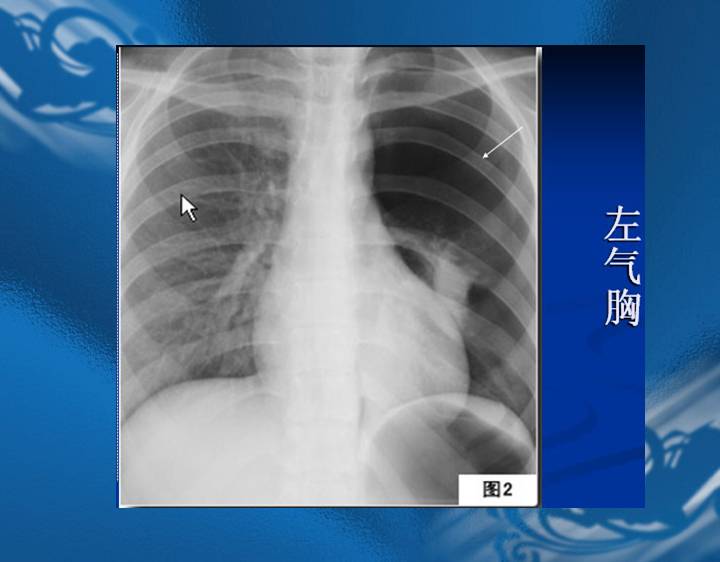

执业医师资格考试“实践技能”影像学辅导资料